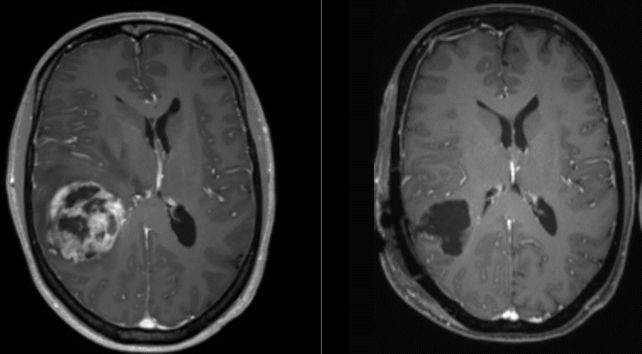

Глиобластома опасна тем, что растёт агрессивно, её трудно обнаружить рано, а также она умеет «выключать» обычный иммунный ответ. Кроме того, до опухоли сложно добраться: она находится в мозге или рядом с другими структурами центральной нервной системы. Опухоль нарушает работу мозга, вызывая отёк, сдавливая здоровые ткани и ухудшая их кровоснабжение.

Нейрохирург Александр Стэг подчёркивает: до испытаний на людях ещё далеко, и метод, вероятно, придётся сочетать с другими препаратами, потому что опухоль может обходить путь STING. При комбинации с иммуноподдерживающими лекарствами у мышей удалось вызвать длительный иммунитет против глиобластомы.